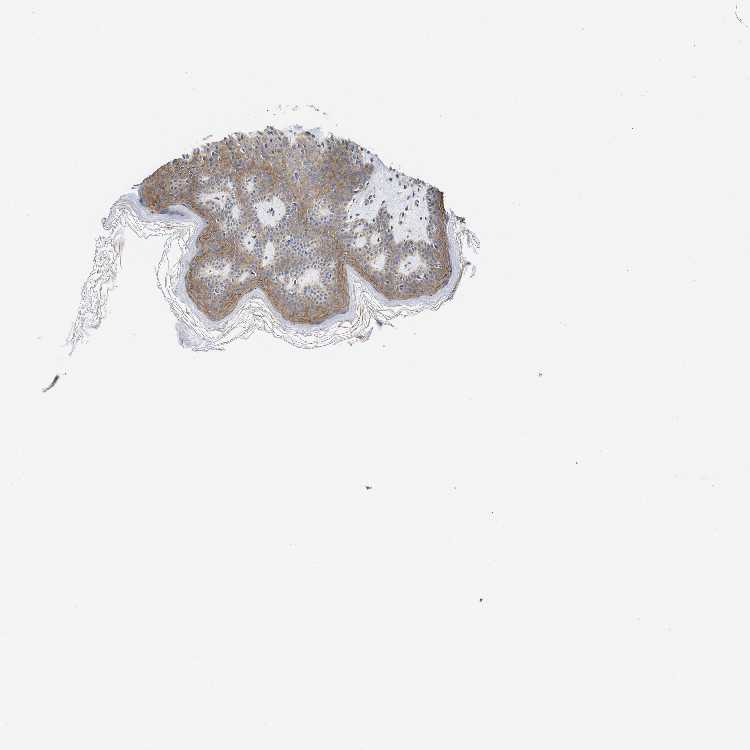

SKIN 1 - Antibody stainingi

Antibody staining in the annotated cell types in the current human tissue is reported as not detected, low, medium, or high, based on conventional immunohistochemistry profiling in selected tissues. This score is based on the combination of the staining intensity and fraction of stained cells.

Each image is clickable and will lead to virtual microscopy that enables deeper exploration of all samples and also displays staining intensity scores, fraction scores and subcellular localization as well as patient and tissue information for each sample.

Antibody HPA019805Antibody HPA020599Antibody CAB004605

Langerhans MediumNot detectedNot detected

Fibroblasts Not detectedLowMedium

Keratinocytes MediumMediumMedium

Melanocytes LowMediumMedium

SKIN 2 - Antibody stainingi

Epidermal cells MediumNot detectedMedium